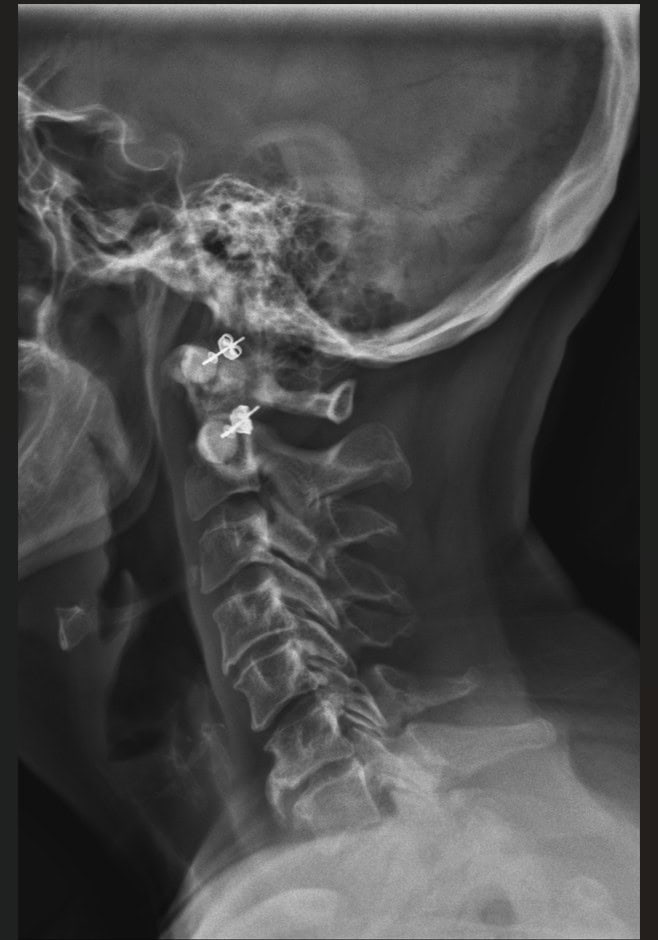

Post Scan